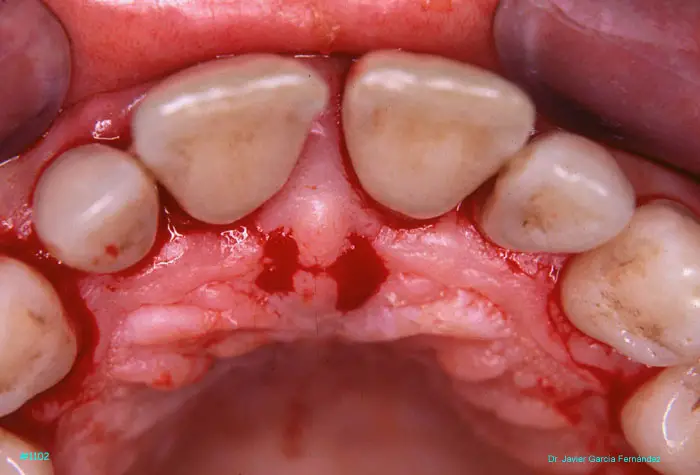

Atlas of Surgical Techniques in Periodontics. Chapter III. Atlas de Técnicas Quirúrgicas en Periodoncia